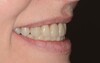

La finition en céramique sur zircone du bridge maxillaire permet un jeu naturel de la lumière sur les dents prothétiques et permet d’éviter en grande partie la fixation des colorations alimentaires.

La fausse gencive rose en céramique permet de recréer la gencive naturelle au maxillaire.